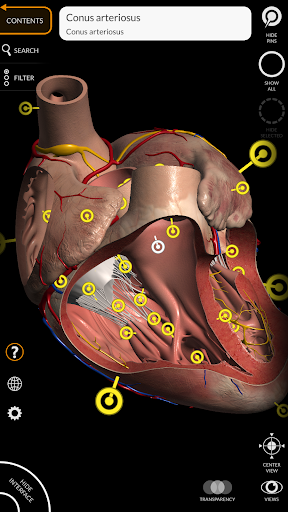

"Anatomy 3D Atlas" vous permet d'étudier l'anatomie humaine de manière simple et interactive.

Grâce à une interface simple et intuitive, il est possible d'observer chaque structure anatomique sous n'importe quel angle.

Les modèles anatomiques 3D sont particulièrement détaillés et avec des textures jusqu'à une résolution de 4k.

La subdivision par régions et les vues prédéfinies facilitent l'observation et l'étude de parties individuelles ou de groupes de systèmes et les relations entre différents organes.

MODÈLES ANATOMIQUES 3D

• Système cardiovasculaire

• Option pour masquer ou isoler un ou plusieurs modèles sélectionnés

• En sélectionnant un modèle ou une épingle, le terme anatomique associé apparaît